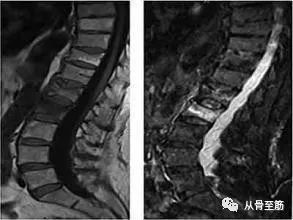

? ? 对于外伤性骨髓水肿,累及负重肢体部位应充分卧床休息,避免关节负重,休息时间要足够长(骨髓水肿一般会在六个月左右才能消退,疼痛持续可能达3-6个月,甚至更长),必要时口服非甾体类抗炎止痛药物,辅以局部理疗,针灸、烤电,超短波等。中药外敷效果也不错。对于椎体骨质疏松压缩性骨折引起的骨髓水肿,可行椎体成形术,止痛效果良好。